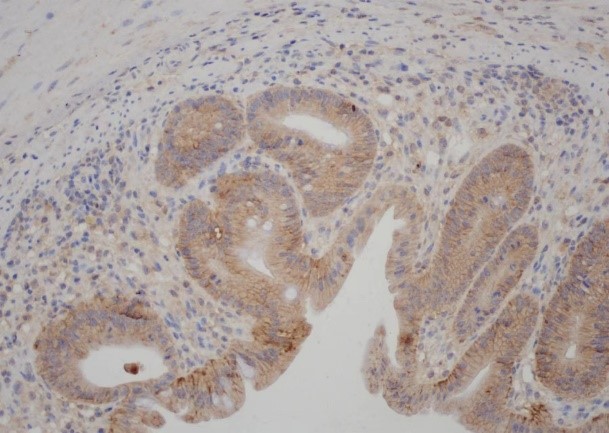

Immunohistochemistry analysis of paraffin-embedded Mouse Colon tissue, using Claudin 1 antibody.High-pressure and temperature Tris-EDTA pH 9.0 was used for antigen retrieval.